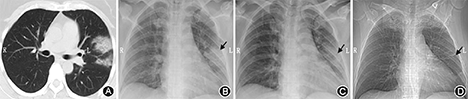

患者女,48岁,既往体健。因"发热6 d"于2020年1月22日来我院发热门诊就诊,胸部CT提示左肺上叶感染考虑(图1A),查2019-nCoV咽拭子核酸阳性,遂诊断"新型冠状病毒肺炎(普通型)"收住本院罗店隔离病房。患者10 d前曾接触来自武汉的同事(该同事事后确诊新型冠状病毒肺炎),6 d前开始出现反复发热,中等度热,最高体温38.9℃,无寒颤,无咳嗽、咳痰,无胸闷、气喘,无头痛、全身酸痛,无腹泻。入院体格检查:体温37.3℃,脉搏93次/min,血压143/97 mmHg(1 mmHg=0.133 kPa),呼吸20次/min,神志清,口唇无发绀,两肺呼吸音粗,未闻及明显干湿啰音,心律齐,双下肢无浮肿。收住后予α-干扰素雾化吸入(每次500万U,加入灭菌注射用水2 ml,每日2次)联合洛匹那韦/利托那韦(200 mg/50 mg,每粒)每次2粒,每天2次抗病毒治疗,莫西沙星片0.4 g,口服,每天1次抗感染,并予以对症治疗。患者入院后多次血化验检查指标范围如下:白细胞(4.09~14.40)×109/L,嗜中性粒细胞0.5~0.8,淋巴细胞绝对值(1.03~1.90)×109/L,血红蛋白114~147 g/L,C-反应蛋白1.8~28.9 mg/L,降钙素原0.041~0.062 ng/ml,红细胞沉降率34~44 mm/h,谷丙转氨酶17~31 U/L,谷草转氨酶24~54 U/L,肌酸激酶49~70 U/L,肌酸激酶同工酶12~32 U/L,乳酸脱氢酶252~473 U/L,血气分析氧分压68.6~82.2 mmHg。患者于收治第3天出现一过性血氧饱和度下降,室内空气未吸氧状态下血氧饱和度93%,伴轻度呼吸困难,体温始终未恢复正常。予鼻导管3 L/min吸氧治疗,并复查床边胸部X线片(1月24日)提示左上肺病灶(图1B)较前进展,结合患者临床表现和胸部影像学变化,临时一次予甲泼尼龙40 mg,静脉滴注治疗。患者次日体温恢复正常,呼吸困难缓解,复查床边胸部X线片(1月25日)提示病灶有明显改善(图1C)。考虑到患者可能对激素治疗较为敏感,此后继续予甲泼尼龙40 mg,静脉滴注,连续治疗5 d后停用。在此期间,患者在室内空气未吸氧状态下血氧饱和度始终维持在97%及以上,无发热,无其他明显不适主诉。于1月31日再次复查床边胸部X线片提示左上肺病灶已吸收(图1D)。于治疗后第12天,复查咽拭子2019-nCoV核酸转阴性,此后再次复核阴性,根据解除隔离和出院标准准许出院[1],院外随访1周,患者无明显不适表现。